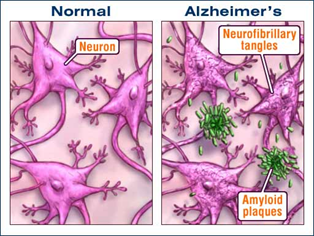

Alzheimer’s disease has been identified as a protein misfolding disease caused by the accumulation of abnormally folded A-beta and tau proteins in the brain. Plaques are made up of small peptides, 39–43 amino acids in length, called beta-amyloid (also written as A-beta or Aβ). Beta-amyloid is a fragment from a larger protein called amyloid precursor protein (APP), a transmembrane protein that penetrates through the neuron’s membrane. APP is critical to neuron growth, survival, and post-injury repair.

In Alzheimer’s disease, an unknown process causes APP to be divided into smaller fragments by enzymes through proteolysis. One of these fragments (Aβ peptide) gives rise to beta-amyloid fibrils, which form clumps that deposit outside neurons in dense formations known as senile plaques. (Figure-1)

AD is also considered a tauopathy due to abnormal aggregation of the tau protein. Every neuron has a cytoskeleton, an internal support structure partly made up of structures called microtubules. These microtubules act like tracks, guiding nutrients and molecules from the body of the cell to the ends of the axon and back. A protein called tau stabilizes the microtubules when phosphorylated and is, therefore, called a microtubule-associated protein. In AD, tau undergoes hyperphosphorylation.

The hyperphosphorylated tau protein begins to pair with other threads, creating neurofibrillary tangles, thus disintegrating the neuron’s transport system.

Figure-1 -showing amyloid plaques and neurofibrillary tangles in Alzheimer’s disease.